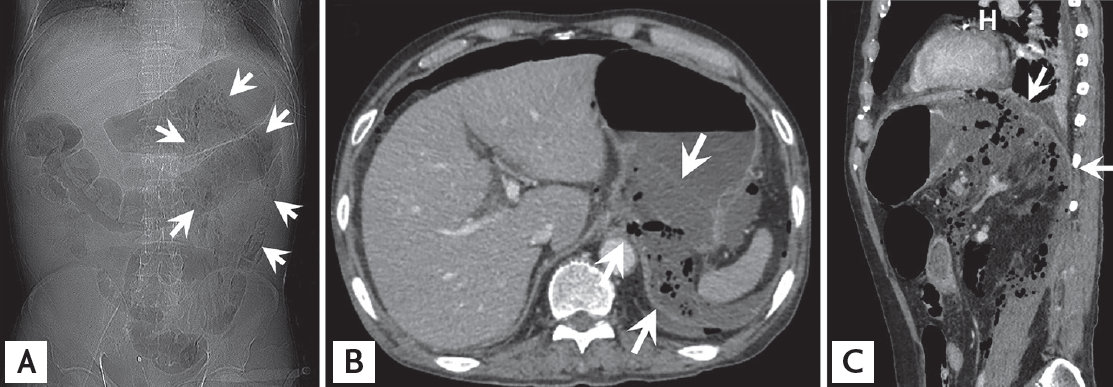

A 74-year-old man presented with a 10-day history of nausea and vomiting. He had been diagnosed as having diabetes mellitus, for which he was followed at a local clinic. Laboratory data revealed hypotension (60/45 mmHg), leukopenia (2,850/µL), and elevated C-reactive protein levels (38.97 mg/dL), which were indicative of sepsis. Although no acute signs or symptoms were observed, immediate computed tomography (CT) study was performed to determine the cause of the sepsis. The scout image showed a collection of mottled gas surrounding a kidney shadow within the left abdomen, indicating a retropneumoperitoneum (Fig. 1A). CT images showed an intramural rim-enhancing fluid collection at the gastric fundus, presumably an intramural abscess. The gastric wall of the esophagogastric (EG) junction and the fundus were poorly visible, and an extensive retroperitoneal abscess and air collections were found within the left anterior and posterior pararenal spaces (Fig. 1B and 1C). We suspected sepsis due to a gastric retroperitoneal perforation, and the patient was referred for emergent surgery. Necrosis of the gastric fundus and EG junction, and profound retroperitoneal inflammation were found during surgery; therefore, a proximal gastrectomy and delayed esophagojejunostomy were performed. Microscopic examination revealed a transmural infarction with a submucosal abscess involving the EG junction and fundus (Fig. 2). The patient was doing well at 1-year postoperative follow-up. Written informed consent was obtained.

Figure 1.

Contrast-enhanced computed tomography images of the abdomen. (A) The scout image shows mottled gas collections surrounding the left kidney (arrows) and extending longitudinally within the left abdomen. (B) Axial and (C) sagittal planes show an intramural abscess of the proximal stomach involving the posterior fundus and esophagogastric junction (B, upper arrow), and an air-containing abscess spreading into the gastric bare area (B, lower arrows; C, arrows) and left anterior and posterior pararenal spaces.